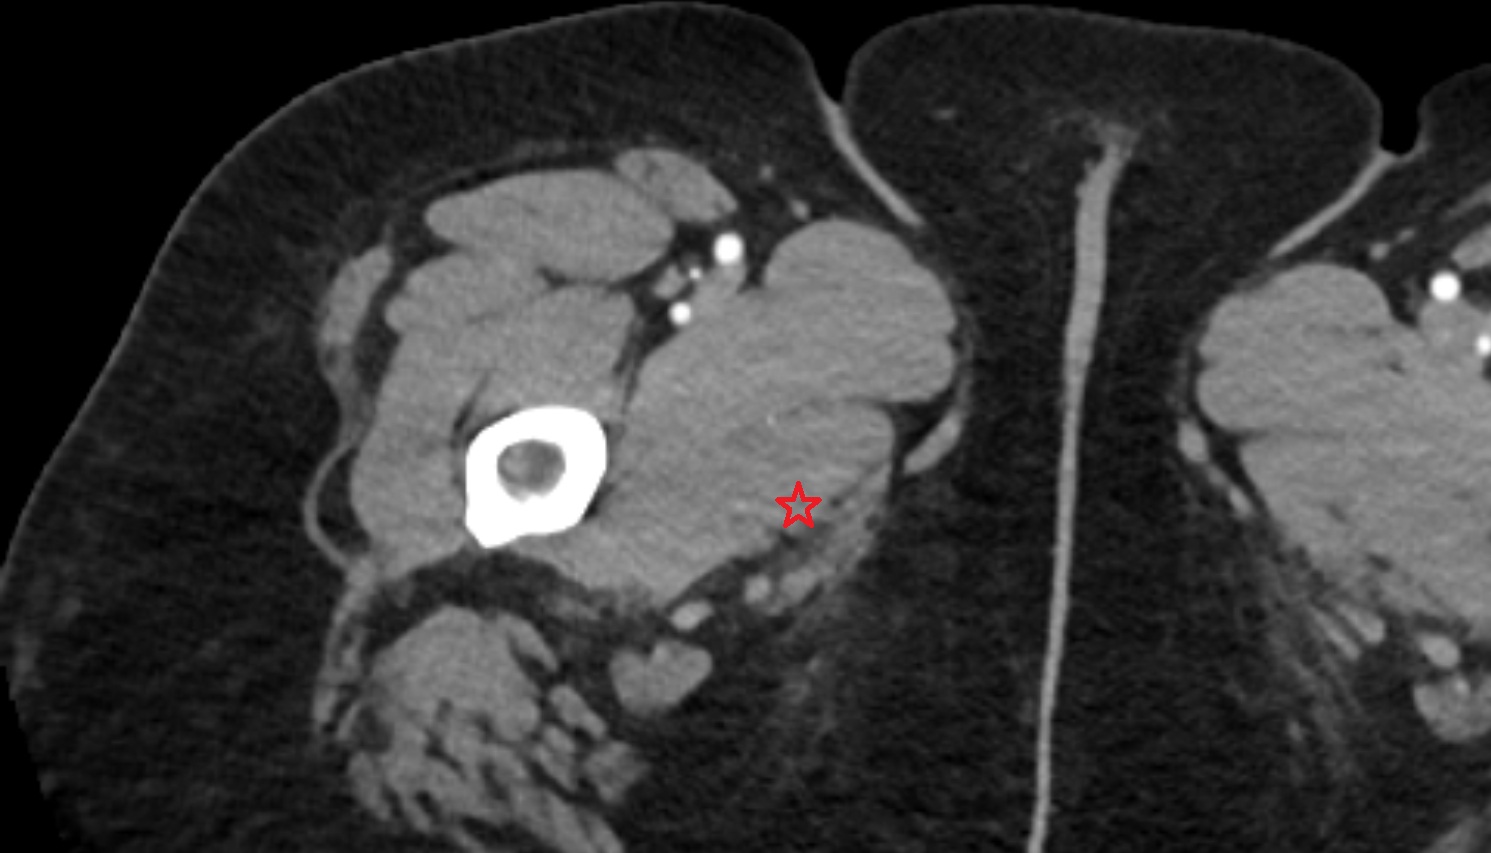

- Sciatic nerve

- Deep femoral artery (profunda femoris)

- Femoral artery

- Superficial femoral artery